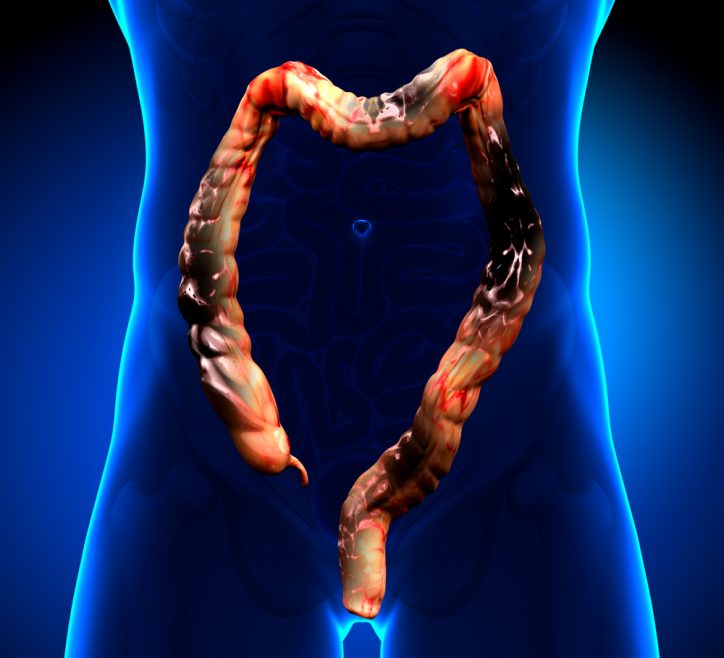

Colon Cancer is the third most common cancer in men after lung and prostate cancer according to the reports from the National Cancer Institute. The reports also find it to be the fourth most common cancer in women after lung, breast and cervical cancer. The symptoms are normally very...

Colon cancer, or colorectal cancer, involves the growth of one or more tumors in the large intestine and rectum. As colorectal cancer is both preventable and treatable, it is important to recognize the symptoms: A change of bowel habits Blood in the stool Diarrhea, constipation, or a feeling that...

What Causes Colon Cancer? Colon cancer is the name given to cancer in the large intestine, usually resulting from the cells of the colon mutating and multiplying to form cancerous polyps on the intestine. Colon cancer is one of the most common cancers identified in both men and women...